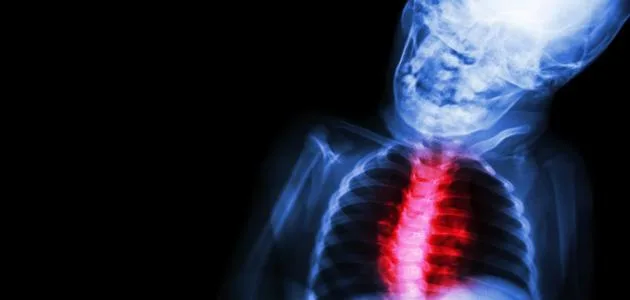

يمكن التعرف على روماتيزم القلب من خلال الأعراض المرتبطة بحمى الروماتيزم. وفي هذا السياق، قال الدكتور أليكس جونسون، طبيب القلب، إن الأعراض تشمل ألم الصدر وضيق التنفس. كما أضاف أن الأعراض قد تختلف باختلاف شدة الحالة.

بينما أكد الدكتور جونسون أن الأعراض الأخرى تشمل التعب والحمى. وكشف أن هذه العلامات قد تشير إلى وجود التهاب في صمامات القلب، مما يستدعي الفحص الطبي العاجل.